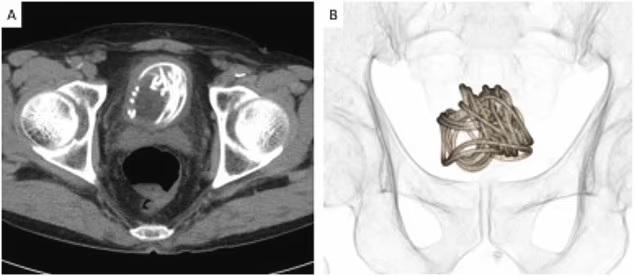

性上癮|日本老翁更嚇人90吋跳繩塞入陰莖

報道指,日本去年11月一個案更加嚇人,一名79歲老翁將90吋長的跳繩塞入陰莖,結果在膀胱內打圈塞住。由於要取出的難度極高,醫生甚至要靠電腦3D圖模擬如何在膀胱開刀取出跳繩。雖然老翁並沒有向醫生解釋為何塞繩入陰莖,但相信他是為了性快感。有英國醫生說,這是他聽過最極端的個案。